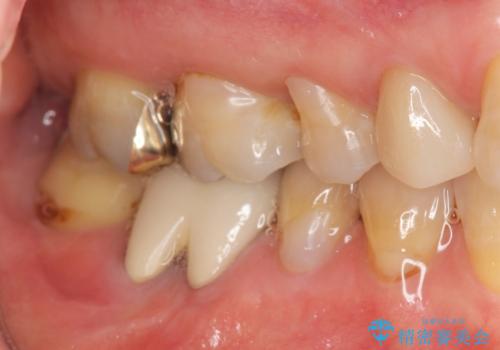

- 右下奥歯からの排膿、痛みの改善を希望され来院されました。

薄い歯質の歯牙に過大な負荷がかかり亀裂を生じ大臼歯分岐部に大きな骨吸収を認め、抜歯を余儀なくされる状態です。

抜歯を行ったのち前後の歯に軽度の動揺があるため、インプラントではなくブリッジによる補綴処置を行い機能回復を行いますが、近心傾斜した第2大臼歯をマイクロインプラントを用いた小矯正を行うことで歯軸方向を改善し、神経を温存した状態でブリッジ製作できるよう前処置を行います。